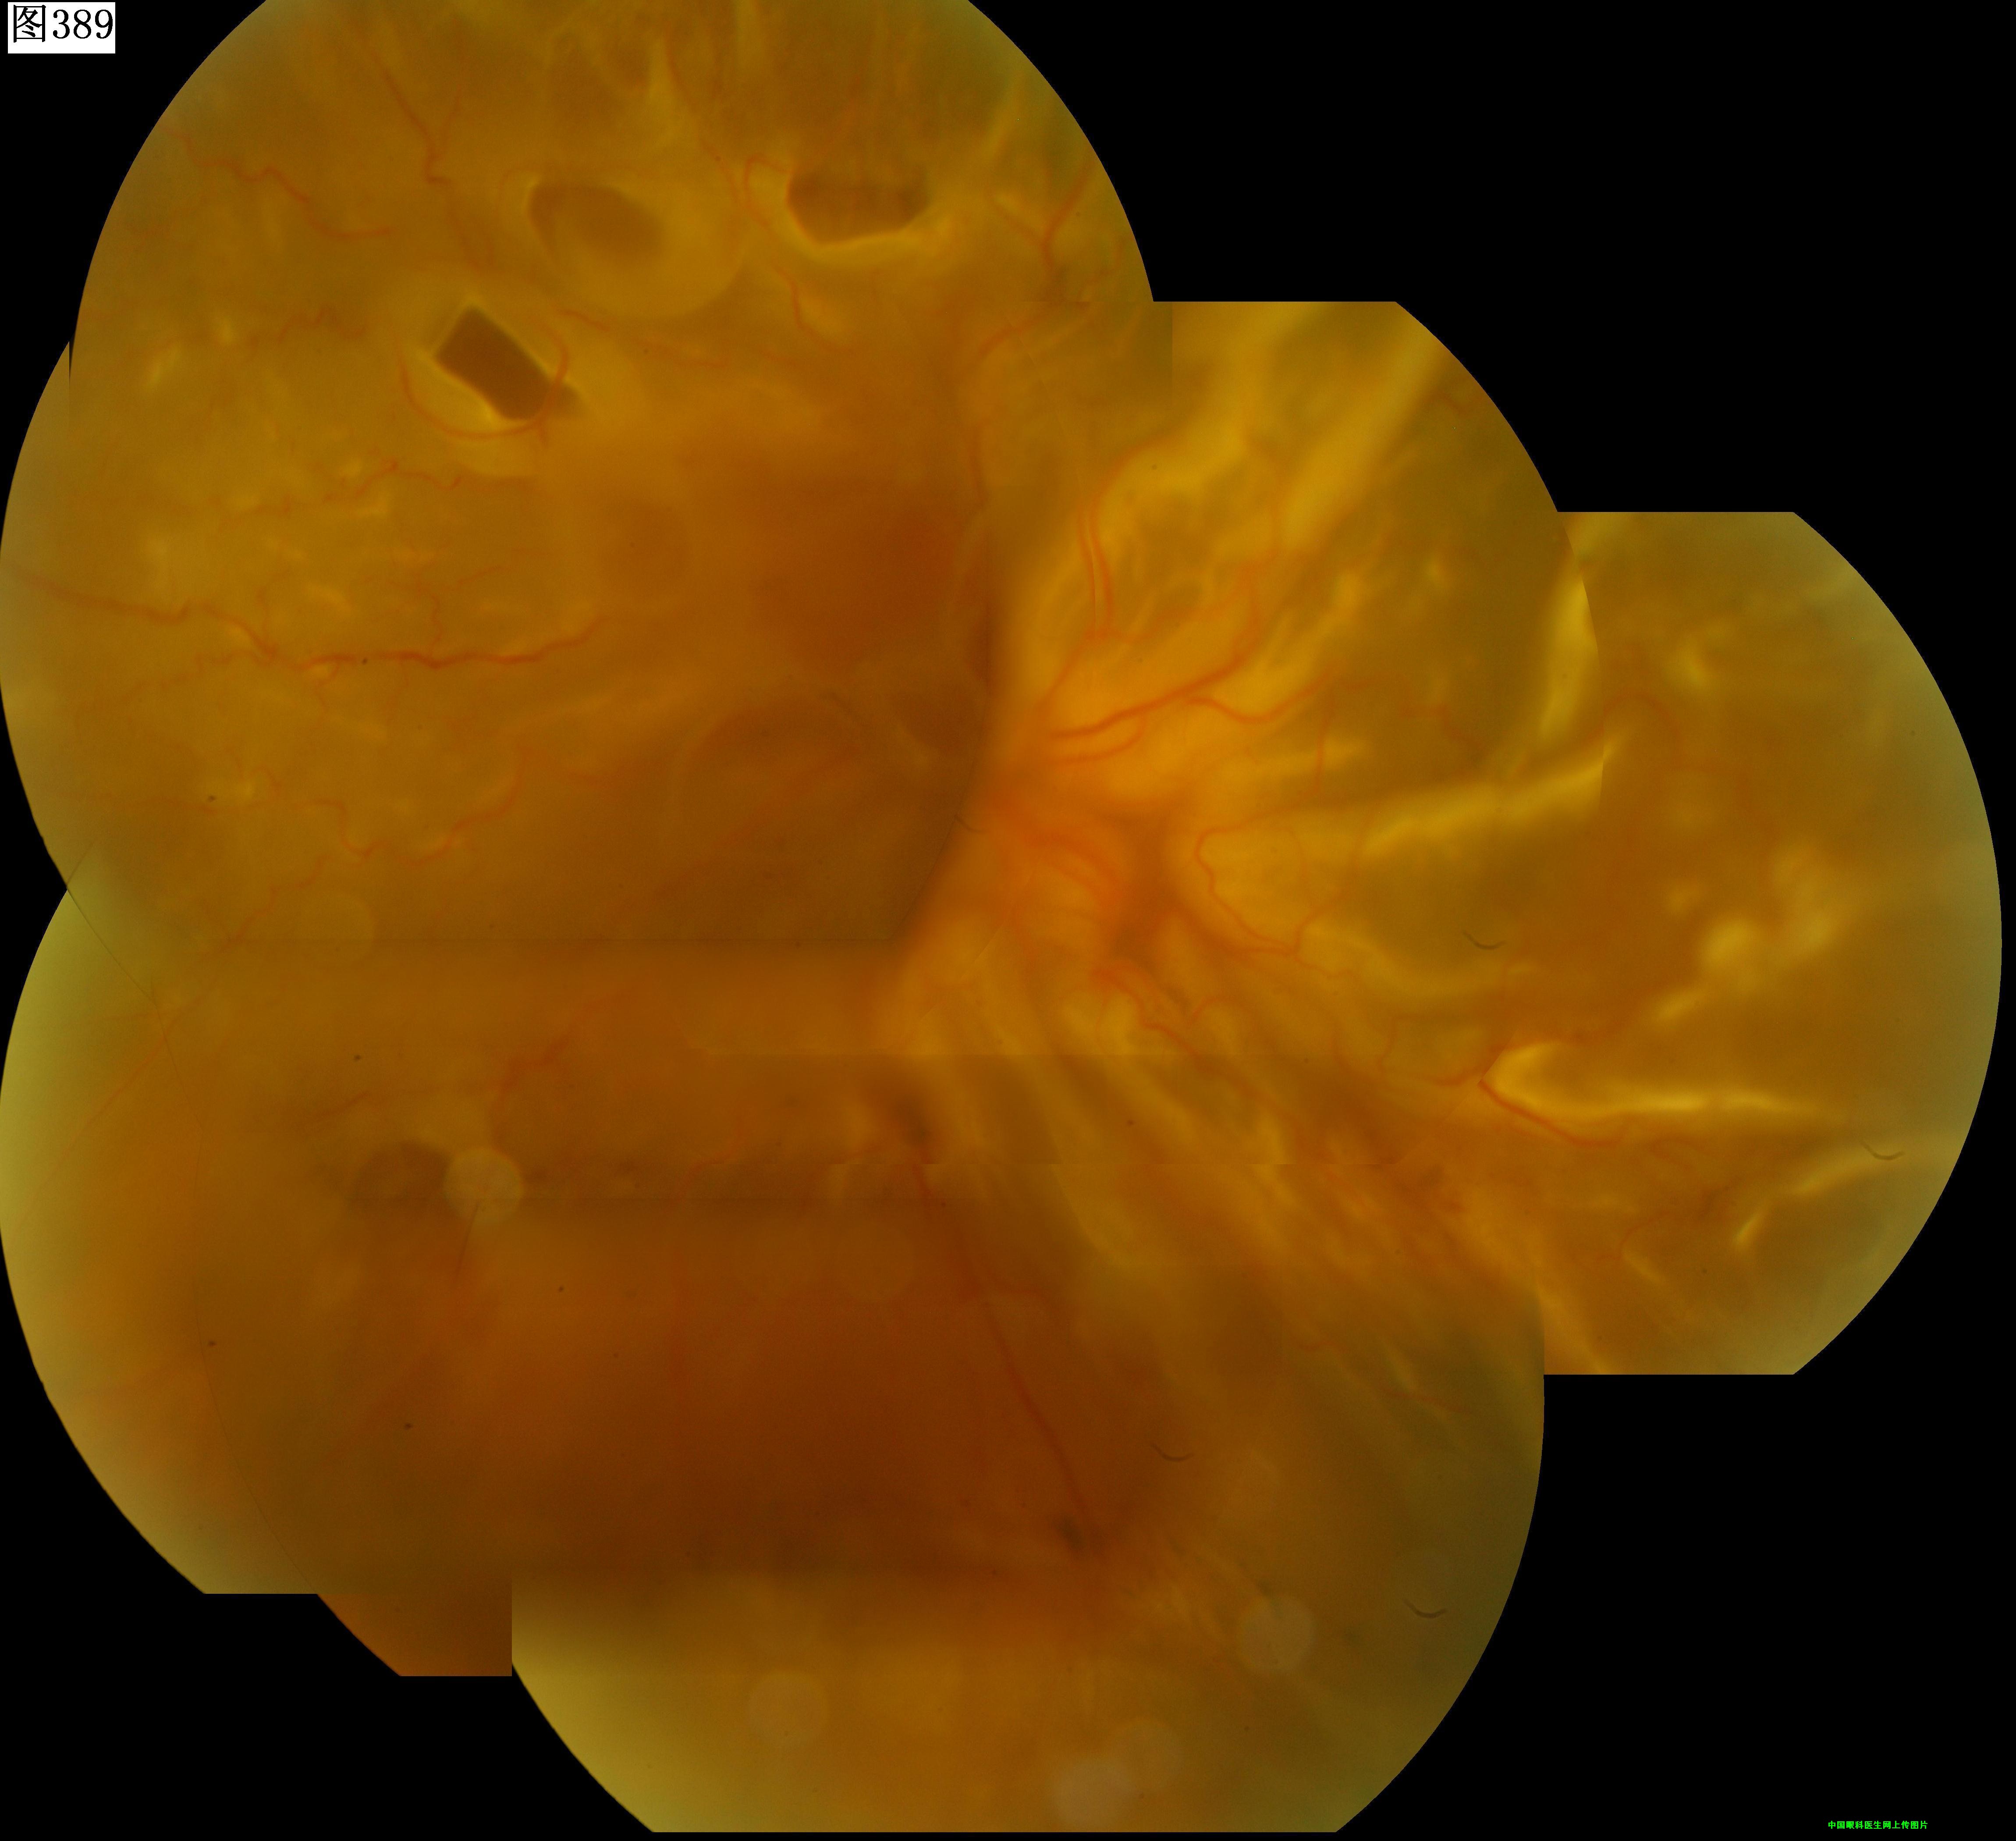

389 390 391 392